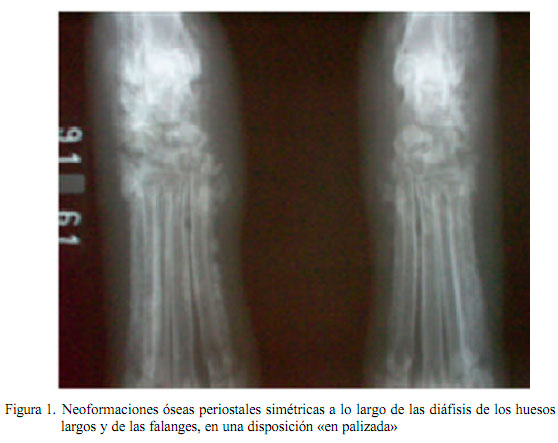

En la placa radiográfica se observan neoformaciones óseas periostales distribuidas simétricamente a lo largo de las diáfisis de los huesos largos y de las falanges. Las primeras alteraciones generalmente aparecen en los huesos metacarpianos y metatarsianos, alcanzando primero el lado medial del segundo dígito y el lateral del quinto dígito (Kealy y McAllister, 2005). El tratamiento consiste en la resección de las neoplasias y el tratamiento de las enfermedades crónicas que estén predisponiendo el proceso.

Al examen radiográfico, en la posición antero posterior de los miembros torácicos y pélvicos, se observó la presencia de neoformaciones óseas periostales simétricas a lo largo de las diáfisis de los huesos largos y de las falanges, en una disposición «en palizada» (Fig. 1). Asimismo, en la evaluación torácica lateral derecha y ventro-dorsal se observaron estructuras nodulares compatibles con neoplasia pulmonar.